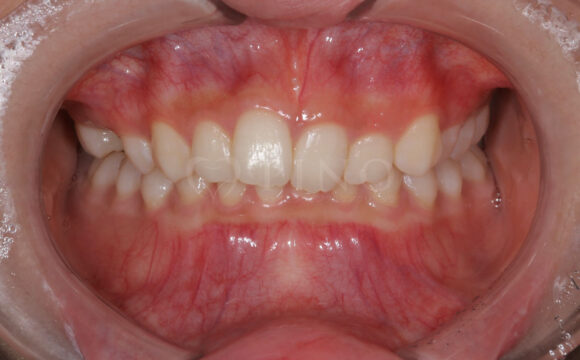

症例5:前歯が噛み合わないのが気になる(20代女性)

主訴 前歯が噛み合わないのが気になる 診断名 開咬 治療方法 マウスピース全顎矯正 抜歯 なし オルソパルス なし 治療期間 1年2ヶ月 費用 749,000円 副作用・注意点 非抜歯での治療のため、歯と歯の間をわずかに削る必要がある、矯正後の後戻りを防ぐためリテーナーの使用が必要となる 備考 奥歯に噛み合わせ不良がない場合、部分矯正が適応となる -